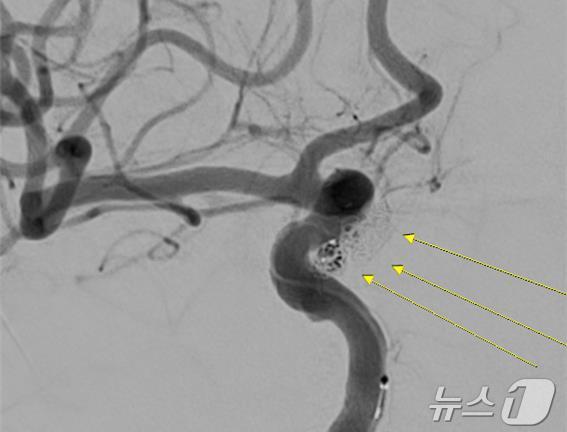

치사율 50% 뇌 지주막하 출혈…"신속한 진단·치료 이뤄져야"

응급 코일 색전술, 두개골 절개 없이 빠른 회복

환자 A 씨의 파열된 대뇌동맥류 코일색전술 사진(센텀종합병원 재판매 및 DB금지)